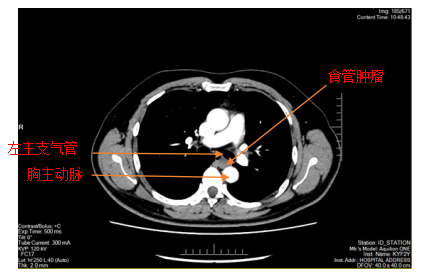

胸部增强CT

患者李某因胸骨后异物感20余天入院,在外院进行胃镜检查提示食管距门齿约26cm处见黏膜下肿瘤,在樱花动漫 超声胃镜提示该肿瘤呈低回声,局限于黏膜下层,固有肌层完整;胸部CT提示该肿瘤直径>2cm,位于食管中下段,增强扫描轻度强化,前与左主支气管相邻,后紧贴胸主动脉,手术过程中稍有不慎就可能发生大出血,危及患者生命,手术难度和风险可想而知。